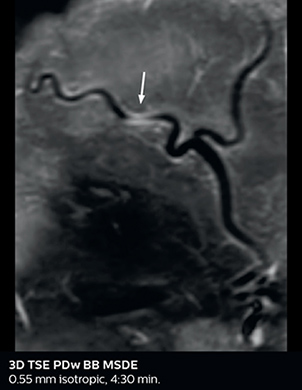

This is an example of acute ischemic stroke with distal occlusion of the right posterior cerebral artery. Note the improved visibility of the ischemic territory on the diffusion weighted image with high b-value. The 3D FLAIR shows a distal PCA occlusion. The fast SWIp depicts the thrombus on the isolated second echo image. The total scan time (including SmartBrain, preparations and a fast 3D T1w TSE Gd) is 8:00 minutes.